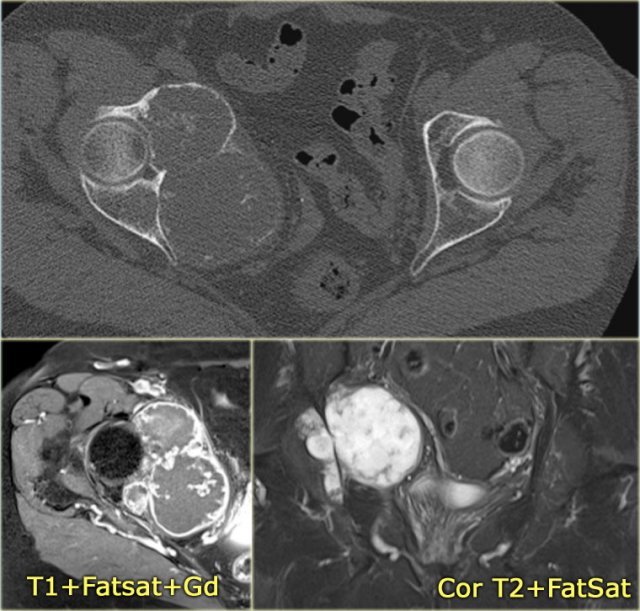

On the left a patient with a chondrosarcoma of the right acetabulum.

On the CT expansion and subtle calcifications are present.

On the coronal T2-weighted image the tumor is seen as a large lobulated mass with very high SI, which is typical for chondroid tumors.

The T1-weighted image after Gd shows typical peripheral nodular enhancement.

In the center there is no enhancement.

This is probably due to a large myxoid component. .

CT shows expansile lesion of the right acetabulum with soft tissue extension.

Subtle calcifications are present indicating chondroid matrix.

CE-T1WI with fatsat shows typical peripheral nodular enhancement.

The central area without enhancement is probably due to a large myxoid component.

Diagnosis: Chondrosarcoma grade 2